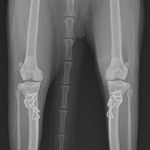

猫の膝蓋骨脱臼(パテラ)

猫も犬と同様に膝蓋骨の問題は起こります。習慣性の膝蓋骨脱臼による異常なメカニカルによる負荷が関節軟骨に生じています。外科的に大腿骨滑車深化術、脛骨粗面移行術によるアライメント手術を行います。また、内科療法としてPRP:自己多血小板血漿を関節内に投与、レーザー照射、カルトロフェン・ベット、NSAIDs、アンチノールなどのサプリメントを継続します。